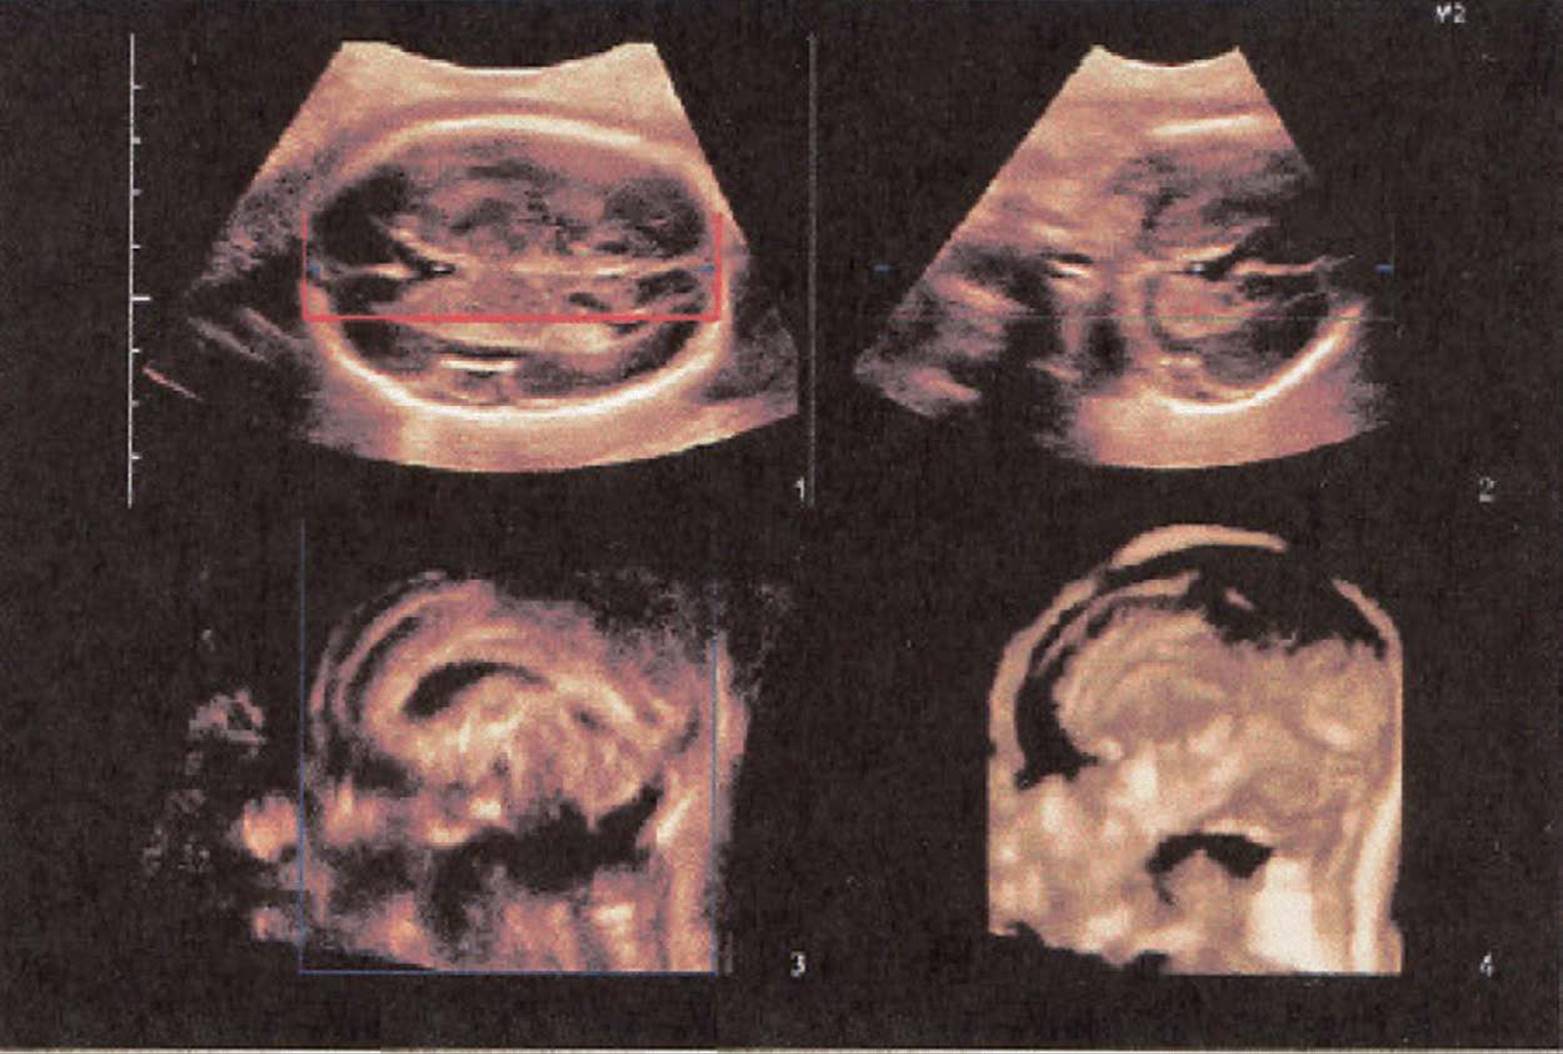

Automated 3D transducer probes contain an array of transducer elements that are swept in a selectable arc through an area of interest. The images are displayed in a multiplanar format with the long-axis, short-axis, and coronal planes, as well as the volumetric image. The multiplanar images are usually displayed with the long-axis view on the top left, followed by the short-axis images obtained at 90° or orthogonal to the long axis displayed in top right, followed by the coronal image scan plane (Fig. 8–3, bottom left). The combined volume is shown, within which (Fig. 8–3 bottom right) the scan plane can be maneuvered.

FIGURE 8–3. Multiplanar imaging format. (Courtesy of Philips Healthcare.): Top left: long-axis plane; Top right: short-axis plane; Bottom left: coronal plane; Bottom right: 3D volume.

FIGURE 8–15. Multiplanar image and 3D reconstruction of the brain of a fetus at 25-weeks’ gestation. The corpus callosum is clearly depicted on the volumetric image (4). (Courtesy of Philips Healthcare.)